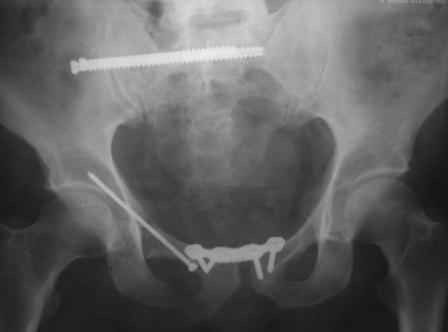

Re: закрытый остеосинтез лонной кости винтом

в архиве нашел подобный случай

С Уважением А.Миронов(Новокузнецк)